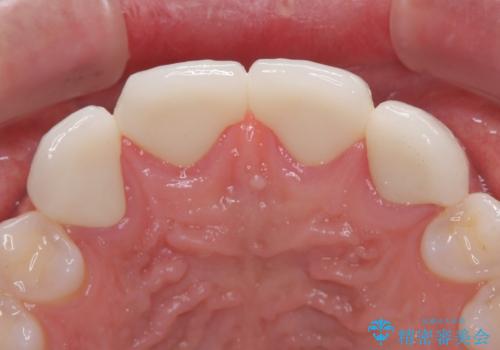

欠損して隙間のある前歯 オールセラミッククラウンで自然な口元に

- 歯の欠損による前歯のすきっ歯を気にして来院された患者様です。

矯正治療かオールセラミックか、治療の選択がありましたが、熟考の末オールセラミッククラウンにて補綴することとしました。

ひとつひとつの歯の幅は非常に大きくなりましたが、手っ取り早く隙間が改善されたとのことで、大変満足していらっしゃいました。